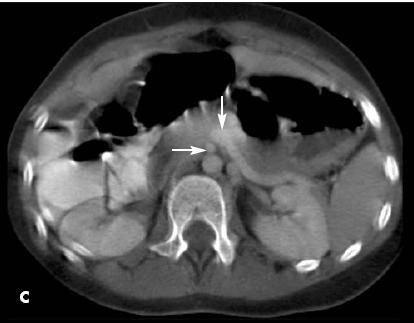

Axial CT images showed an appendicolith (A) and, 9 mm inferiorly, a tubular structure with intraluminal air and surrounding inflammatory changes in the left lower quadrant (B). These findings were consistent with appendicitis. Another view (C) showed that the superior mesenteric vein (SMV) (vertical arrow) joined with the splenic vein to form a portal confluence that rotated to the left of the superior mesenteric artery (SMA) (horizontal arrow). This finding was consistent with GI malrotation. The duodenal- jejunal junction was identified to the right of the vertebral column (not shown).

CT findings of acute appendicitis can include an enlarged caliber (greater than 6 mm in maximal transverse dimension), pericecal and periappendiceal inflammatory changes, phlegmon, extraluminal gas, and an appendicolith. 2 Congenital intestinal malrotation on CT can be determined by transposition of the SMA and SMV, with the SMA on the right side of the SMV, near its origin from the aorta.3